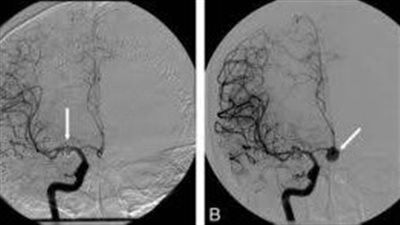

أطباء مستشفى التأمين الصحي الشامل ببورسعيد ينقذون حالتي "تمدد وريدي بالمخ"